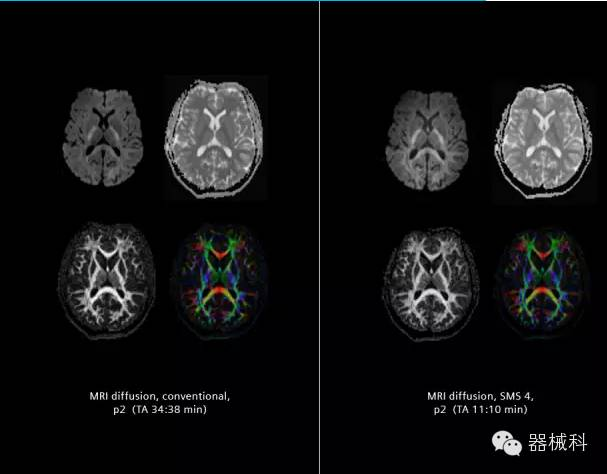

在2015年RSNA上,西門(mén)子隆重發(fā)布了Simultaneous Multi-slices 技術(shù)(即同時(shí)多層采集技術(shù),簡(jiǎn)稱(chēng)SMS),這是磁共振掃描技術(shù)中第一次引入“同時(shí)多層”的概念,此概念技術(shù)的發(fā)布,將對(duì)未來(lái)磁共振成像領(lǐng)域帶來(lái)巨大的變革!

· 2012年,麻省總醫(yī)院Kawin Setsompop等在西門(mén)子7T 磁共振上獲得了使用SMS技術(shù)的得到的同時(shí)多層diffusion和fMRI圖像,并得出結(jié)論,采用全新的SMS技術(shù),可以大幅度提高空間分辨率和采集速度。

·美國(guó)國(guó)立衛(wèi)生研究院(NIH)的人類(lèi)連接組項(xiàng)目(HCP)由于需要采集大量的人腦數(shù)據(jù),第一次在HCP3.0T磁共振(基于Skyra 3.0T)上與西門(mén)子合作開(kāi)始嘗試使用SMS技術(shù)。作為項(xiàng)目的一部分,SMS在提高圖像質(zhì)量、增加彌散成像方向數(shù)、改善功能成像時(shí)間采集效率方面有重大貢獻(xiàn),也為HCP計(jì)劃迅速公布數(shù)據(jù)立下了汗馬功勞。

SMS技術(shù)可以將原本用于科研的高級(jí)成像技術(shù)轉(zhuǎn)化成臨床常規(guī)。

SMS可以有效提升高級(jí)功能成像精準(zhǔn)度。

擁有了SMS“同時(shí)多層”采集技術(shù)之后,用戶可以在非常短的時(shí)間內(nèi)完成MR掃描,結(jié)合西門(mén)子靜音技術(shù),大大提高患者的舒適性,或在單位時(shí)間內(nèi)采集更多的數(shù)據(jù),也可以得到高精度、高準(zhǔn)確性、大數(shù)量的功能成像數(shù)據(jù),為臨床和科研提供強(qiáng)大的支持。專(zhuān)家認(rèn)為,SMS“同時(shí)多層”采集技術(shù)未來(lái)在 提高成像質(zhì)量、外科手術(shù)計(jì)劃、降低術(shù)后神經(jīng)功能缺陷、提高fMRI的時(shí)間采集效率、提高靜息態(tài)功能磁共振數(shù)據(jù)質(zhì)量等方面將帶來(lái)深遠(yuǎn)影響,希望該技術(shù)可以盡早面世,引領(lǐng)磁共振進(jìn)入多層時(shí)代!